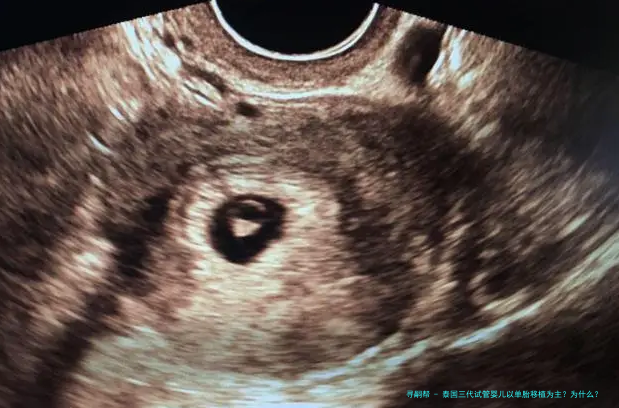

随着多个胎儿条件的放开,女年纪的增长,很多家庭去泰国做试管婴儿,因为要的是多胎,在进行胚胎移植的时候建议移植了一个胚胎。如此,泰国三代试管婴儿以单胞胎移植为主?为什么?下方跟随来一起了解一下吧。

泰国三代试管婴儿以单胎移植为主?为什么?

对于条件理想的患者,括移植2个有可能双胎妊娠的患者,或者因体重、子宫异常不能承受双胎妊娠的这么一部分患者,一般是建议进行单囊胚移植,既能保证她们的妊娠率,也能减低期的各种风险。

对于条件稍差的患者。比如:高龄、巢储备差,或者患子宫肌瘤、腺肌症等情况的患者,这些不利因素会影响胚胎着床率。那么,在这种情况下,会移植2个胚胎增加女方怀的机会。但,若是后期出现问题,从安全的因素考虑,请务必减胎。